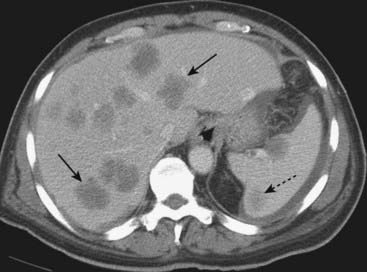

image

Figure 18-31 Metastases to the liver and spleen.

Metastases usually appear as multiple, low-attenuation masses (solid black arrows). There are also low-attenuation lesions in the spleen (dotted black arrow). The patient had a primary adenocarcinoma of the colon.

imageMetastases are the most common malignant hepatic masses. While most are multiple, metastases also represent the most common cause of a solitary malignant mass in the liver.

image Most liver metastases originate in the gastrointestinal tract, particularly the colon, and almost all reach the liver via the bloodstream. Other primary sites of metastatic spread to the liver include stomach, pancreas, esophagus, lung, melanoma, and breast.

image Recognizing liver metastases on CT and MRI:

Metastases are usually multiple, low-attenuation masses (Fig. 18-31). Larger metastases may demonstrate areas of necrosis that can be recognized as mottled areas of low attenuation within the mass. Mucin-producing carcinomas, such as might originate in the stomach, colon, or ovary, can calcify both the primary tumor and the metastases (see Fig. 16-14).